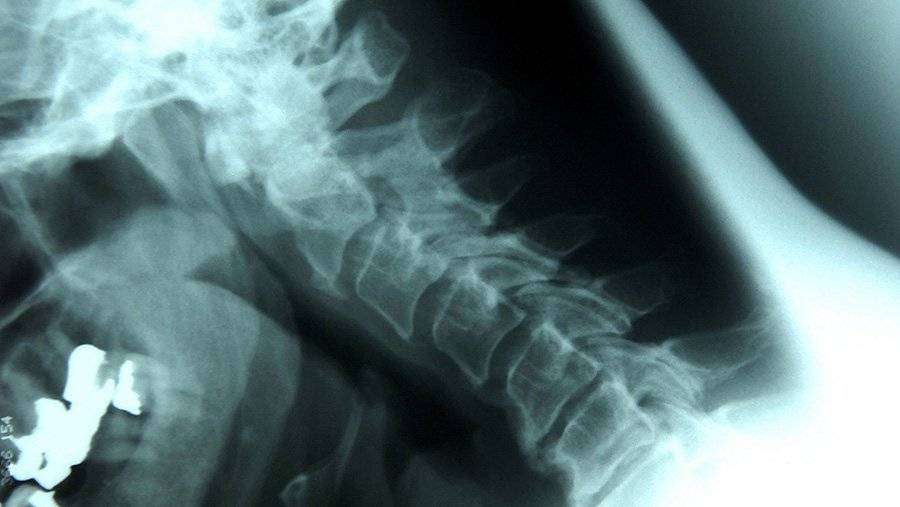

Медики назвали шесть вредных для позвоночника привычек

Эксперты рассказали о шести привычках, негативно сказывающихся на позвоночнике и приводящих к нарушению кровообращения, болезням сердца, мозга и органов пищеварения. Об этом сообщил портал «МедикФорум».

Самой первой вредной привычкой стало курение. Из-за него в межпозвоночных дисках задерживаются кровоток и лимфа. На втором месте оказалась привычка сутулиться, поскольку такое положение позвоночника с возрастом становится опаснее из-за постоянной нагрузки на внутренние органы.

Отказ от молочной продукции занял третье место антирейтинга, поскольку после 45 лет организму человека очень важно получать кальций. Отсутствие молочных продуктов в рационе ведет к разрушение костей и позвоночника в том числе.

Четвертой вредной привычкой стала любовь к кофе, который буквально вымывает из костей кальций и делает кости слабыми.

Также на здоровье позвоночника негативно сказывается малая подвижность. Помимо этого эксперты рассказали об опасности долгого использования гаджетов. По их словам, это приводит к смещению межпозвоночных дисков.